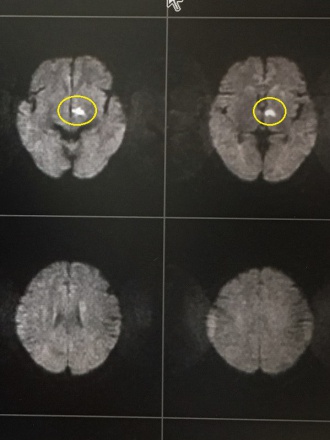

マラソン中に右手足の軽い麻痺が続く男性が受診され、頭部MRIで脳梗塞を認めました。幸い麻痺は軽く、すぐに入院できる病院に紹介しました。話を詳しく聞くと、前日から体調不良で血圧がいつもより高かったようです。

MRI画像の黄色い丸印が、脳梗塞の部位です。